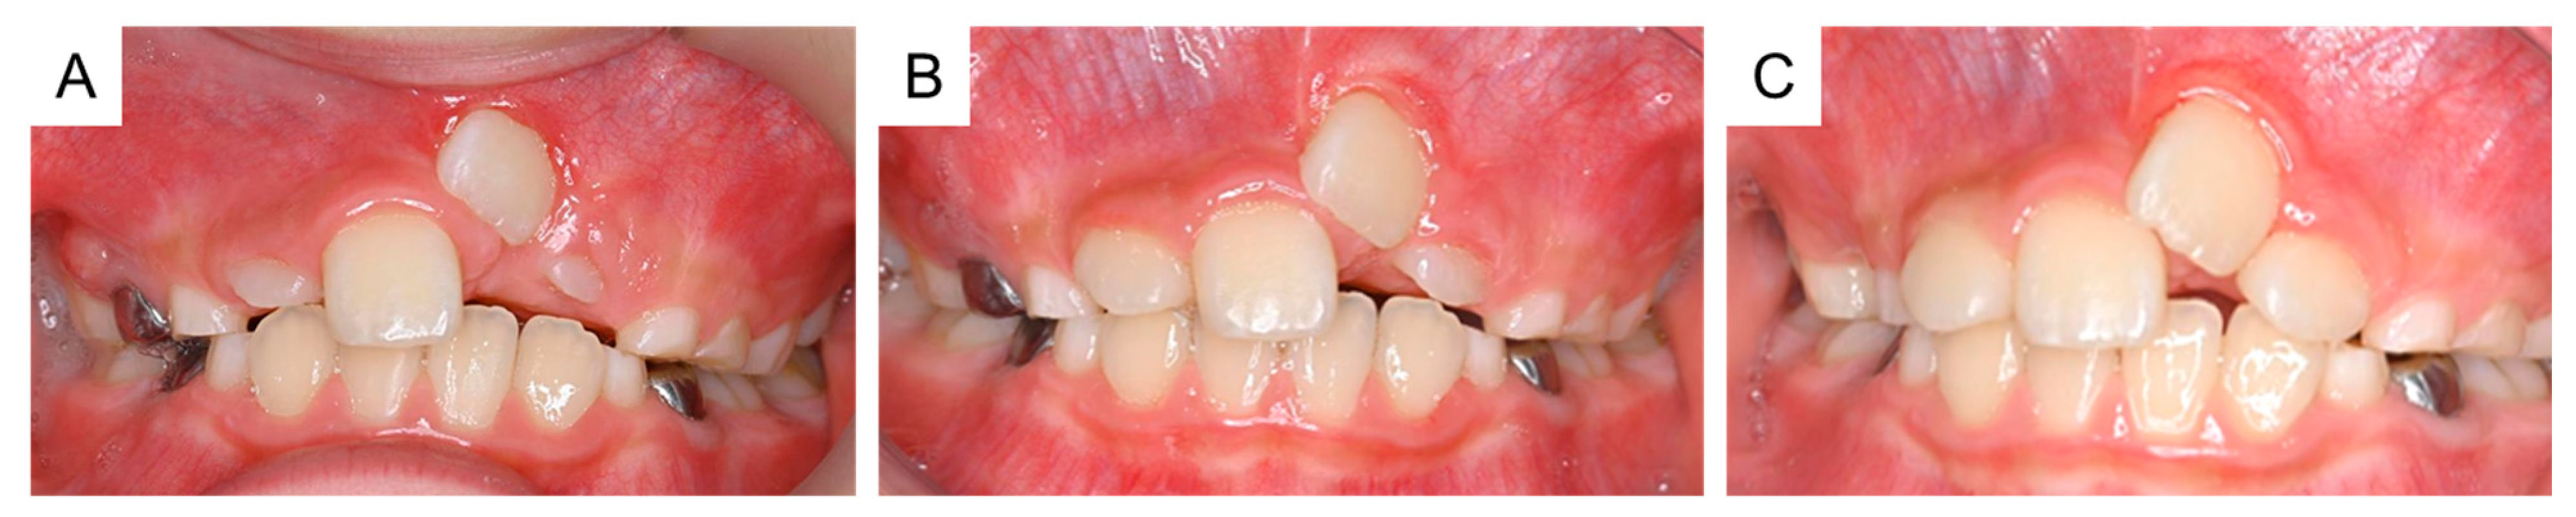

By the time the patient was aged 8 years and 2 months, the permanent maxillary left central incisor had not erupted in the oral cavity (Figure 3A). A periapical radiograph revealed the presence of a calcified tissue near the crown of the permanent maxillary left central incisor (Figure 3B). Considering the difference in the eruption time of the bilateral permanent maxillary central incisors, we decided to take an immediate surgical approach. One month later, we surgically removed the calcified tissue and the bone covering the permanent maxillary left central incisor under physical restraint. The extracted calcified tissue measured 5 mm × 5 mm (Figure 3C). Histopathological examination showed the presence of a tooth-like structure with enamel, dentin, pulp, and reduced enamel epithelium, confirming the diagnosis of a third supernumerary tooth (Figure 4).

Figure 3. Extraction of the third supernumerary tooth. (A) Intraoral photograph at the age of 8 years and 2 months. (B) Periapical radiograph showing the third supernumerary tooth at the age of 8 years and 2 months. (C) Extracted calcified tissue, which was later diagnosed as the third supernumerary tooth. Scale bar: 5 mm.